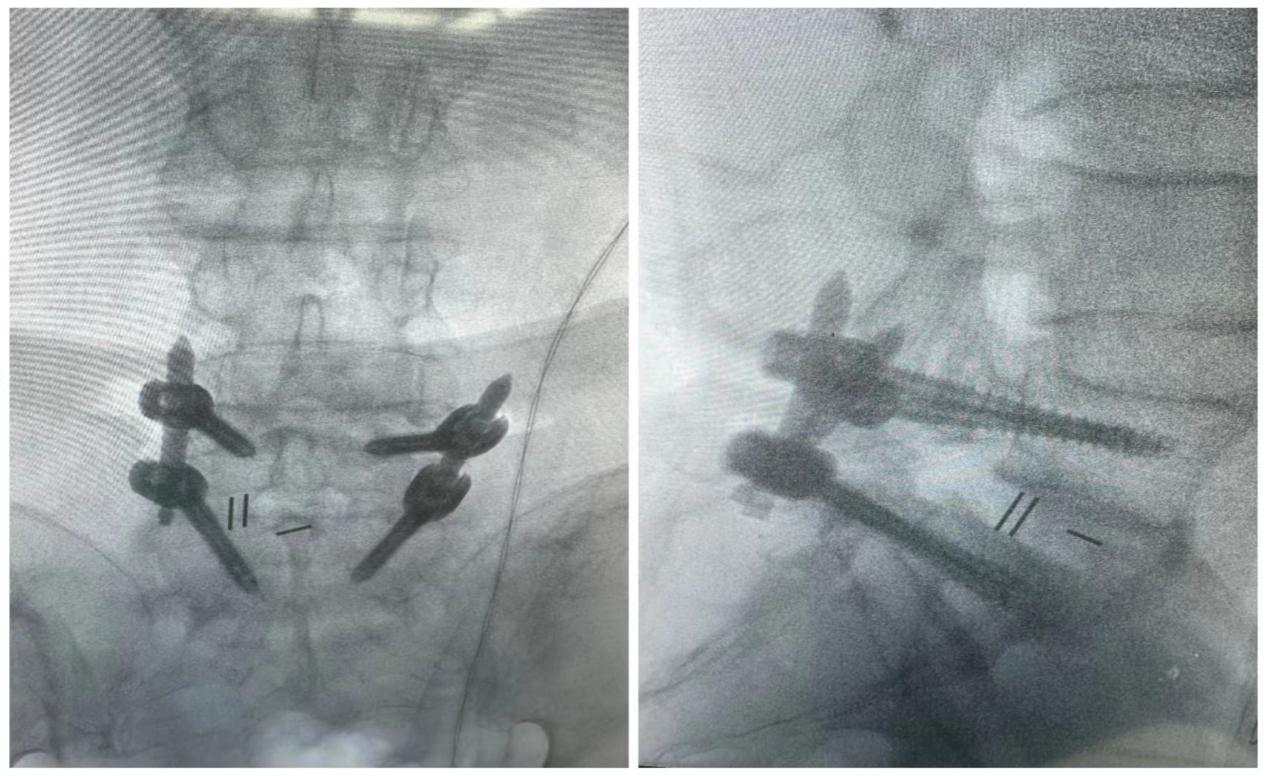

ORTHBOT脊柱机器人术前设计及术中穿刺

患者术后影像学资料